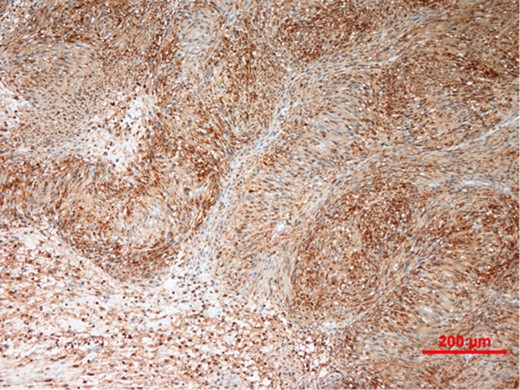

Our patient underwent an excisional biopsy without a preoperative needle biopsy. A 1.2 × 1.2 × 0.8 cm smooth well-encapsulated nodule was removed in entirety from the breast parenchyma. On bisection, the cut section displayed a pale pink smooth homogeneous appearance. Microscopic evaluation showed an encapsulated spindle cell tumour with prominent nuclear palisading and features typical of a schwannoma (Fig. 3). There was also strong and diffuse positive staining of S-100, favouring the diagnosis of schwannoma (Fig. 4). There was no evidence of malignancy in the specimen.

Immunohistochemistry showing tumour cells staining strongly and diffusely for S-100 protein.